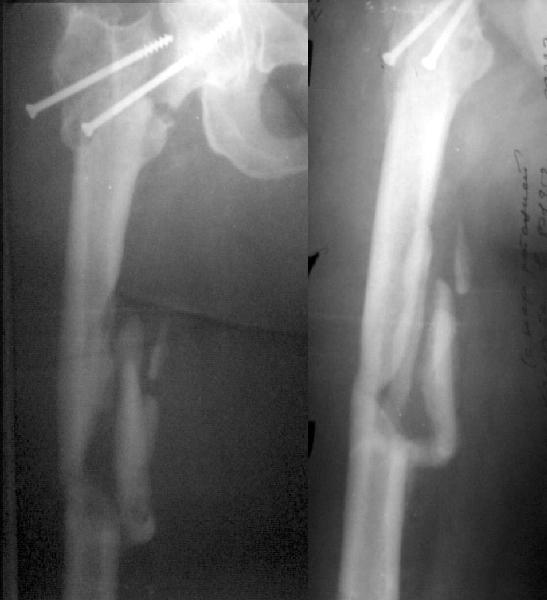

Примерно год назад женщина 44 лет оперирована по поводу перелома шейки и диафиза бедра через 2 нед. после автоаварии. Сделали закрытый остеосинтез бедра стержнем и попытались синтезировать шейку мимо гвоздя.

Пролучилось плохо (снимок N1, через 1 мес. после операции), отчасти благодаря тому, что окружность бедра в верхней трети у нее больше 80 см. Гвоздь на днях удален через старые разрезы. Шейка, понятное дело, не срослась, а диафиз - только на ограниченном участке (снимок N2).Встает вопрос - что делать дальше? Думаем про вальгизирующую остеотомию с фиксацией клинковой пластинкой. Может быть, с ретроградным штифтованием бедра (хотя места между переломом и нижним концом пластинки маловато). Эндопротез с длинной ножкой не доступен. Ожирение - прежнее. Заранее спасибо.

This is a good example of sub optimal placement of the neck screws. Young patients with neck/shaft combo fxs have a high Pauwells' angle. This is counteracted by open reduction and internal fixation in order to reduce caudal portion of fem neck. The screws are angled differently by placing them perpendicular to the fem neck fx line (typical AO technique) or horizontal to the floor. The screws here are similar to elderly fem neck fx types. Therefore, no biomechanical advantage exists and the nonunion is produced.

You need to perform a valgus osteotomy with 130 osteotomy plate. This will improve the relative Pauwells' angle and improve the union rate. Problem is the probable nonunion or partial union to the shaft. The osteotomy plate is

only made with 6 holes which will not allow for bypassing the shaft problem.

You will probably require an open plating and bone grafting. Try to angle your distal ost and prox shaft screws so that they overlap and theoretically decrease the stress riser created with the double plates.

The biggest problem here is the femoral neck nonunion in a 44 yo obese (?weight) patient. No femoral head AVN apparent on plain xray but a significant fracture gap with a verticle fracture line on AP. If you can get that to heal you will be doing her a great service. The femoral shaft is still secondary.

Сделали подвертельную вальгизирующую остеотомию (чуть низковато плучилось), синтезировали клинковой пластинкой. После компрессии и

латерализации винтом ниже остеотомии, нижний винт в пластинке заменен на 3 монокортикальных. Бедро ретроградно рассверлили и заштифтовали UFN 12 мм, верхний запирающий винт ввели через пластинку. Псевдартроз сдавился хорошо. Снимок в приложении. Буду рад услышать комментарии.

The valgus osteotomy has improved the position of the femoral neck fracture

:-)

The blade plate is in the anterior and proximal aspect of the femoral head

:-(

What activity level is planned? Keep a close eye on the femoral head and neck. They will determine outcome, primarily.